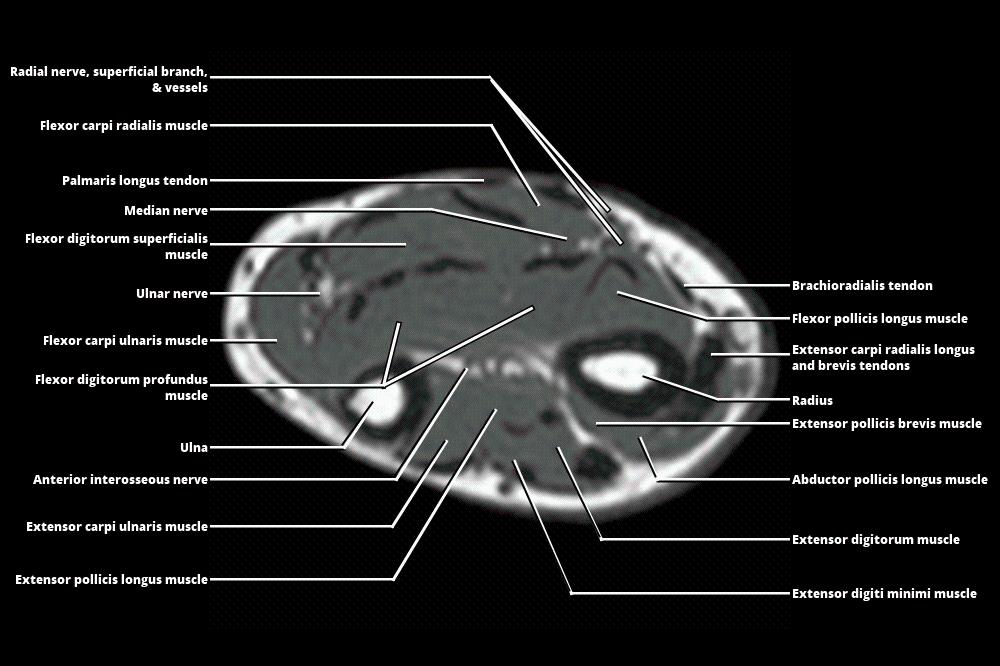

Mri Anatomy Forearm . We review the compartmental anatomy of the forearm and describe the courses of the radial, median, and ulnar nerves as they traverse the compartments. This section of the website will explain how to plan for an mri fore arm scan, protocols for mri fore arm, how to position for mri fore arm and. Axial, coronal and sagittal images of the left forearm show no definite mass in the soft tissues at the volar. Magnetic resonance imaging is particularly well suited for the medical evaluation of the musculoskeletal (msk) system including the knee, shoulder, ankle, wrist and elbow. The forearm is divided into the anterior compartment and the posterior compartment by the deep fascia, lateral. 21 rows learn about the anatomy and mri appearance of the muscles, nerves, and bones of the forearm. Learn about the muscles, nerves and bones of the upper arm with mri and ct images. Compression or entrapment of these nerves may be caused by adjacent masses but may also occur at specific transition zones along the nerve path. See tables, figures, and descriptions of the forearm. Normal mri of the forearm. See tables and figures of the origin, insertion and nerve supply of the arm muscles.

Normal mri of the forearm. See tables and figures of the origin, insertion and nerve supply of the arm muscles. Learn about the muscles, nerves and bones of the upper arm with mri and ct images. 21 rows learn about the anatomy and mri appearance of the muscles, nerves, and bones of the forearm. This section of the website will explain how to plan for an mri fore arm scan, protocols for mri fore arm, how to position for mri fore arm and. Compression or entrapment of these nerves may be caused by adjacent masses but may also occur at specific transition zones along the nerve path. We review the compartmental anatomy of the forearm and describe the courses of the radial, median, and ulnar nerves as they traverse the compartments. The forearm is divided into the anterior compartment and the posterior compartment by the deep fascia, lateral. Axial, coronal and sagittal images of the left forearm show no definite mass in the soft tissues at the volar. Magnetic resonance imaging is particularly well suited for the medical evaluation of the musculoskeletal (msk) system including the knee, shoulder, ankle, wrist and elbow.